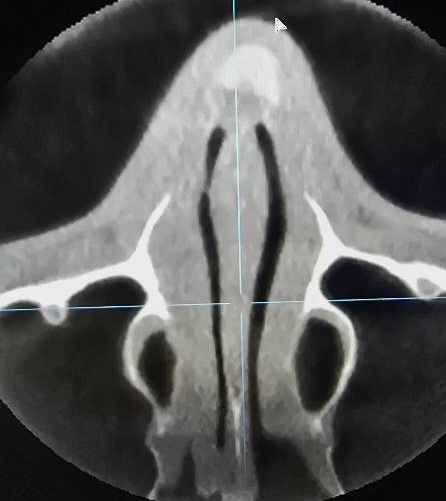

2 ตรวจดูทรงซิลิโคน จมูกไม่สวยซักที CTบอกได้ เพราะ การตรวจด้วยเครื่องเอกซเรย์คอมพิวเตอร์ความละเอียดสูง สามารถบอกได้ว่าปัญหาความไม่สวยเกิดจากอะไร ทรงSILICONEจมูก ยาวหรือสั้นเกินไป SILICONEตรงหรือโก่ง หัวใหญ่หัวเล็ก การตรวจด้วยเครื่องเอกซเรย์คอมพิวเตอร์ความละเอียดสูง บอกได้ทั้งหมด จะเห็นว่ารูปทรงของSILICONE เมื่อเสริมเข้ามาจริงๆแล้ว ยังต้องมีการปรับตัวให้เข้ากับเนื้อเยื่อรอบด้านทำให้ไม่สามารถประเมินจากภายนอกเพียงอย่างเดียวได้

3 ความเสี่ยงของการทะลุ ในกรณี มีการดันของซิลิโคนมากเกินไปจนผิวหนังบางขึ้น การตรวจด้วยเครื่องเอกซเรย์คอมพิวเตอร์ความละเอียดสูง สามารถบอกได้ โดยเฉพาะอย่างยิ่งการทะลุจากด้านในรูจมูก พราะส่วนใหญ่ของการทะลุไม่ได้เกิดบริเวณผิวด้านนอก แต่เกิดด้านในรูจมูก ซึ่งยากต่อการตรวจสอบ